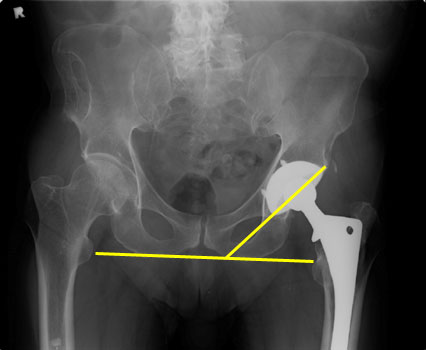

AKA Horizontal version, acetabular angle of abduction, theta angle.

• Normal 40 +/- 10 degrees

• Shallow angles result in limited abduction of hip, with subsequent difficulty with perineal care and intercourse

• Steep angles increase risk of dislocation